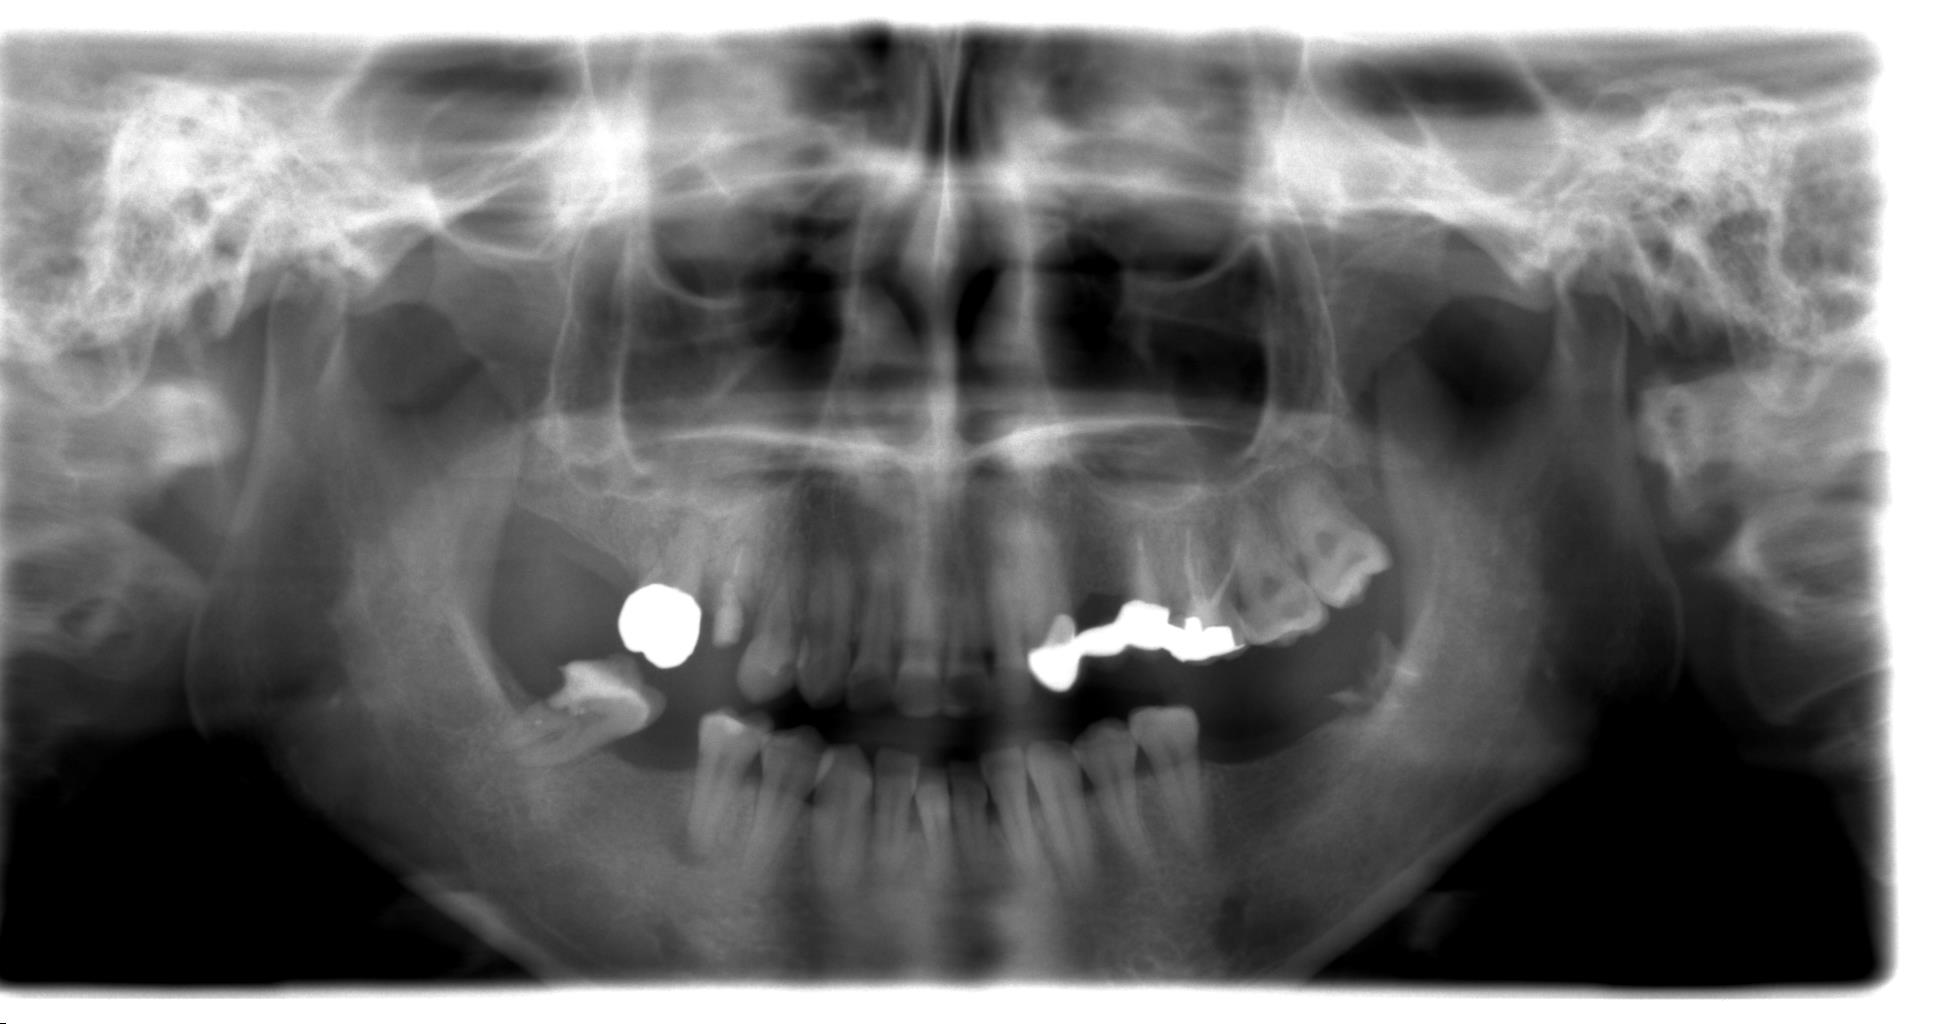

症例01

30代 女性 奥歯を失い歯並びが変わってきた

術前レントゲン

術後レントゲン

| 主訴 | 奥歯が咬めなくて前歯が出てきた。 奥歯を治療したあと、咬み合わせがもし落ち着いたら前歯も治療したい。 |

| 年代・性別 | 30代 女性 |

| 治療部位 | 下顎両側 67 |

| 治療費用 | インプラント 420,000円×4本 静脈内鎮静法 75,000円×2回 |

| 治療期間 |

10ヶ月 |